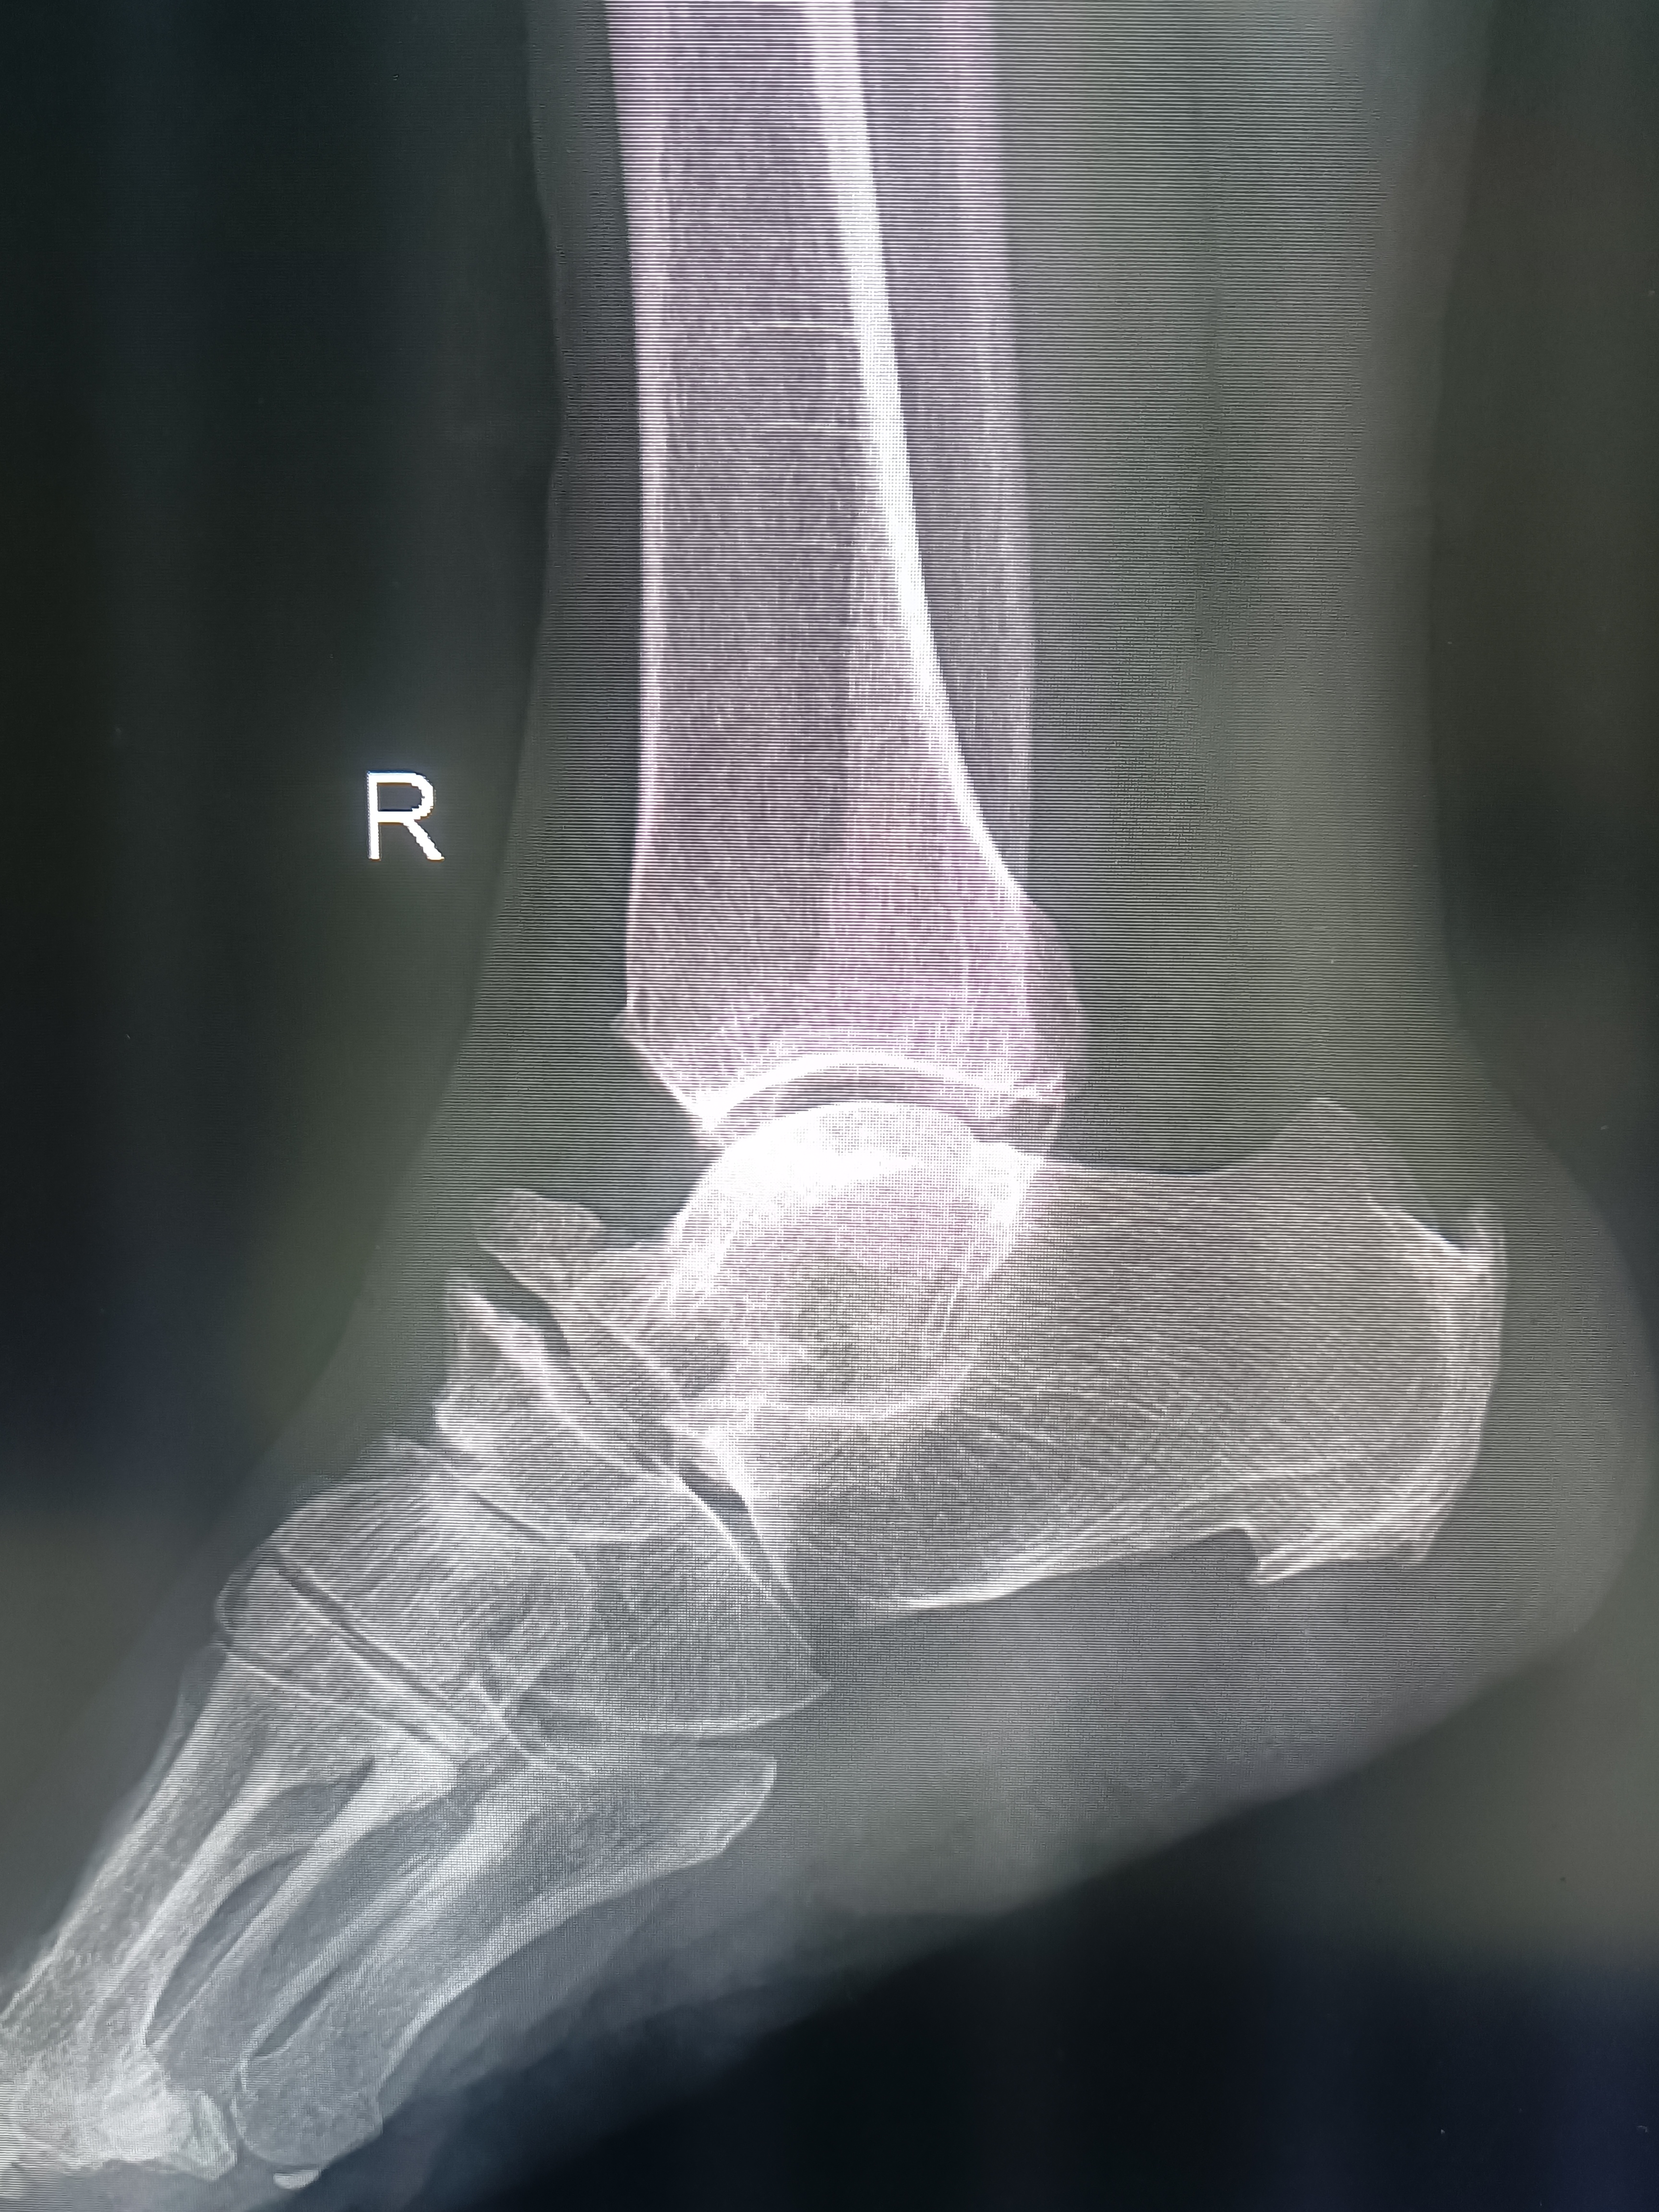

双足踝疼痛病例分享!